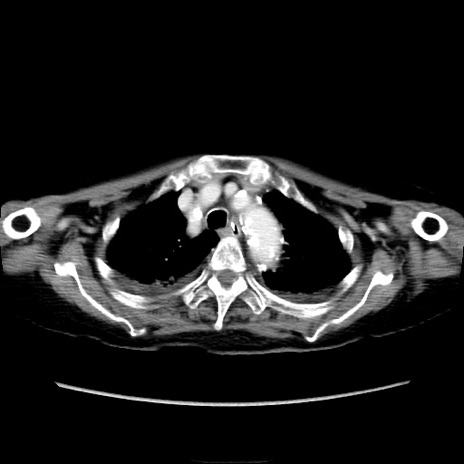

症例40(横断像)

【症例】90歳代女性

【主訴】腹痛・嘔吐

【現病歴】 食欲低下、嘔吐があり昨日他院受診。肺炎と診断され入院となる。入院後より腹部全体に圧痛あり。胃管留置され経過みていたが、症状持続するため、

当院転院となる。

【既往歴】胸椎圧迫骨折、胆石症

【身体所見】腹部:中央に激痛あり、圧痛あり、反跳痛不明

【データ】WBC 17100、CRP 18.82

他院CT